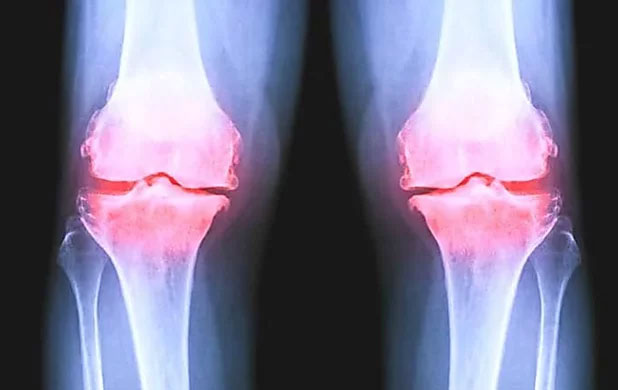

Ontdek welke wetenschappelijke doorbraak volgens toonaangevende artsen de eerste werkzame therapie voor artrose is. En hoe duizenden patienten al binnen enkele weken permanent en zonder bijwerkingen van hun gewrichtspijn afkwamen met de gewichtsontgifting methode.

Ik ontdekte een baanbrekend onderzoek van deUniversiteit van Californië gepubliceerd in december 2022 waarin werd onderzocht 277 mensen met een matige tot ernstige kniegewrichtsontsteking die minimaal een jaar lang regelmatig ontstekingsremmende pijnstillers slikten.

MRI-onderzoeken wezen dat uit gewrichtsontsteking bij degenen die nemen pijnstillers verergerd aanzienlijk meer dan vier jaar.

Hun kraakbeen is afgebroken veel sneller dan in de vergelijkingsgroep die geen pijnstillers slikte.